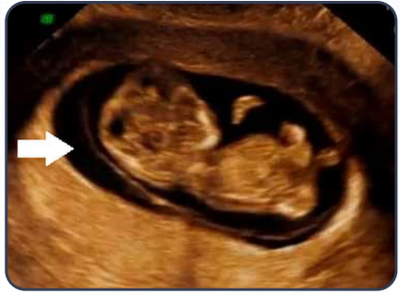

Gestante comparece a emergência com queixa de sangramento vaginal, indolor. A idade gestacional atual é de 11 semanas pela data da última menstruação e de 10 semanas por ultrassonografia realizada há duas semanas. Ao exame especular, visualiza-se colo íntegro e sangramento discreto pelo orifício cervical externo. Ao toque vaginal, percebe-se o útero amolecido, globoso, colo fechado. Nesse atendimento, foi realizada ultrassonografia que constatou atividade cardíaca fetal com frequência de 168 bpm, conforme imagem a seguir.

Assinale a alternativa que descreve a estrutura indicada pela seta.